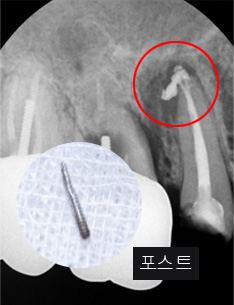

신경관이 막혀 있는 경우 재 신경치료로 낫지 않는 경우, 포스트가 있어 재 신경 치료를 할 수 없는 경우, 치아 뿌리까지 염증이 심하지만 이러한 염증을

제거 할 수 없는 경우, 고운미소 치과에서는 치조골 주위 염증조직을 제거하는 치근단절제술을 시행합니다.

기존 포스트 제거 후 근관내 약재 삽입

재 신경치료(난이도 상)